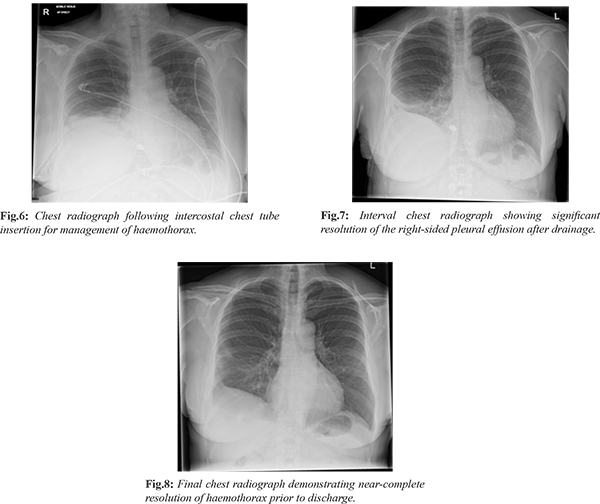

The patient was transferred to the resuscitation area, where an intercostal chest tube was inserted [Fig.6], yielding approximately 1000 mL of blood. Following cardiothoracic consultation, she was admitted under the surgical team for further management. Her clinical condition improved progressively [Fig.7,8], and the chest tube was removed after seven days. She was discharged in stable condition with planned follow-up in the surgical outpatient clinic.